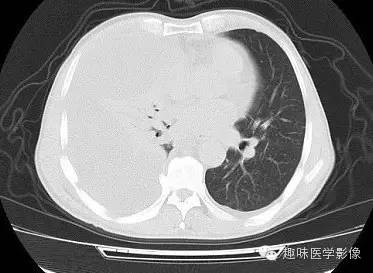

CT: 右侧胸廓缩小。右肺上叶前段结节,略分叶,可见长短不一毛刺,胸膜牵拉征及血管集束征,右肺组织向肺门萎陷,左肺清晰,未见异常。纵隔内见淋巴结肿大(4R淋巴结增大)。右侧前壁及侧后胸壁包裹性积液征象。

右上肺周围型肺癌,纵隔淋巴结转移,胸膜腔包裹性积液。

3)空泡征是肺癌典型的CT影像,肿瘤直径小于3cm时,瘤体中央会出现多个1-2mm大小的点状低密度影,或多个影像融合。同时伴有纵隔、胸膜的转移,本例CT上可见4R淋巴结增大,胸膜腔包裹性积液。